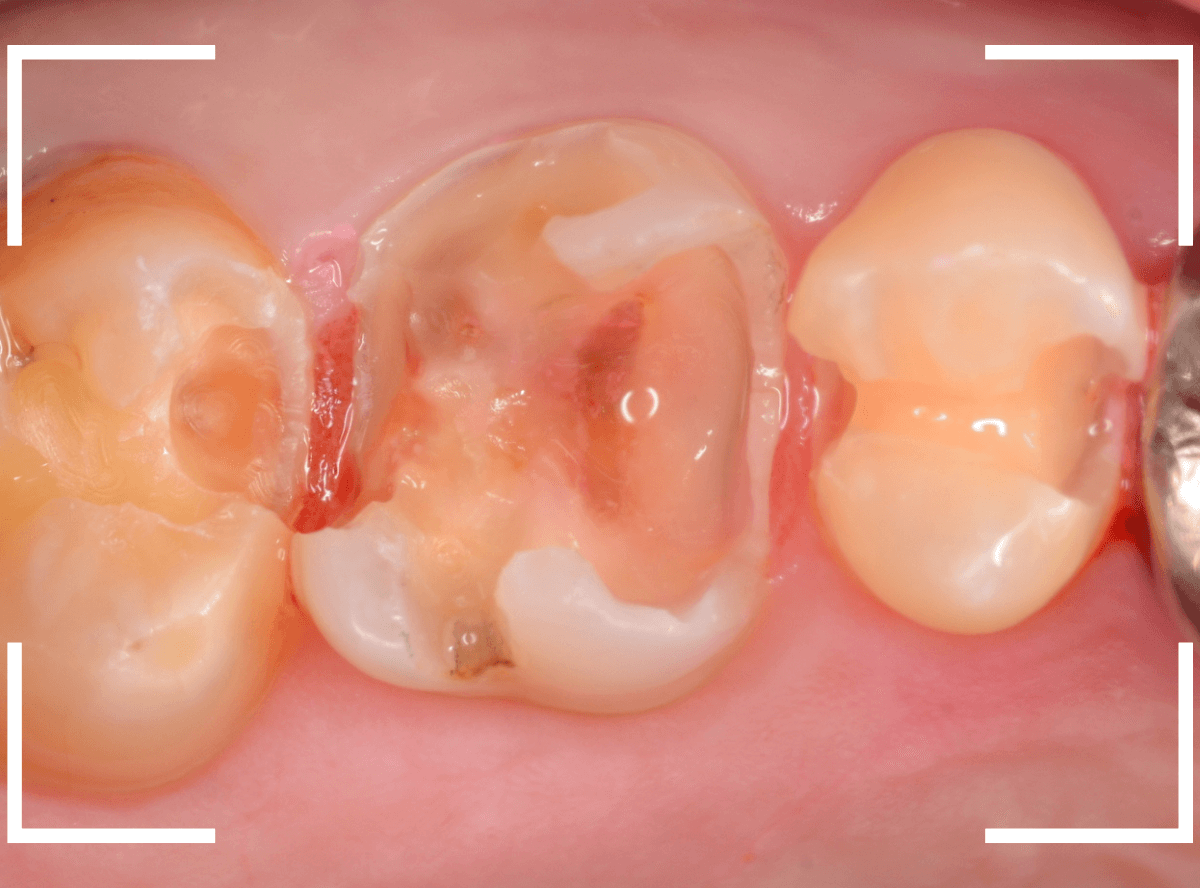

Case.16 金属の周りであちこちから虫歯

検診を希望された患者さんのケースです。

お口の中を拝見すると、上の奥歯の歯のすき間(隣接面)や、変色したレジンの中が怪しい感じです。

レントゲン写真で確認します。

青い線が神経で、赤い線が虫歯と思われる部分です。

奥から3歯が虫歯と思われますが、特に中央の歯の虫歯が深そうです。

まず、中央の歯の金属を除去します。

〇部分は前の治療時にしいたセメントです。この下に虫歯が広がっていると思われます。

セメントを除去したところです。

赤く染め出されているところが虫歯です。

神経に近くなっていますので、診療に虫歯を除去します。

側面のレジンや隣の歯との間の虫歯も慎重に除去します。

かなり広く虫歯が広がっています。

奥の歯の虫歯も全て除去しました。

3歯すべての虫歯を除去したところです。

しばらくお薬をつめて症状を経過観察した後、型どりをしてつめものを再製作する予定です。